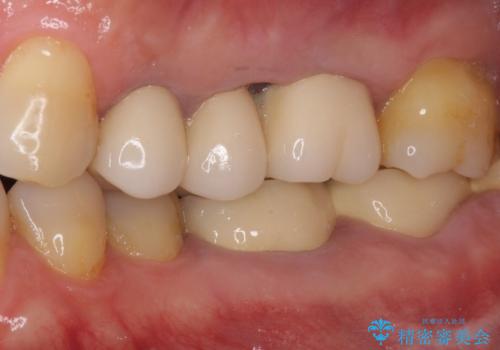

ものが挟まって痛む 割れてしまった歯のオールセラミックブリッジ治療

抜歯後、骨吸収量が多く、歯肉のラインが不揃いとなっているため骨造成術を、硬い歯肉が失われて清掃性が低下するため角化歯肉の移植術を行い、また並行して支台歯の根管治療を行っていき、環境を整えた上でオールセラミックブリッジにて補綴治療を行うこととしました。

インプラントによる補綴治療も検討しましたが、骨吸収量が多いこと、後方の支台歯が今後抜歯となる可能性が否定できないことを鑑み、将来抜歯となった際にインプラント2本を埋入することで患者様と事前にお話をしました。